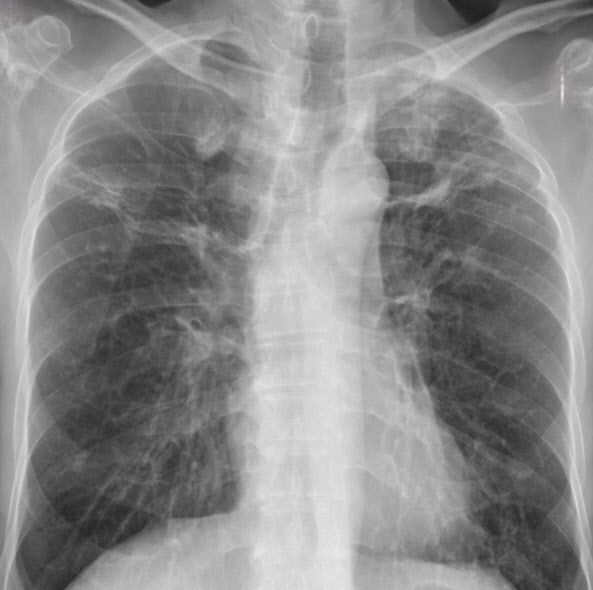

의협은 한의사 측의 X레이 사용이 무면허 의료행위로서 환자에게 피해를 줄 수 있다고 경고하기도 했다. 의협은 “학문적 기초가 다른 한의사가 의학을 바탕으로 한 진단행위를 함으로써 발생하는 오진으로 환자가 적절한 치료를 받지 못한다면, 이는 명백히 보건위생상 위해를 발생시킨 무면허 의료행위에 해당한다”고 강조했다.

의협은 “ 한의학적 원리를 기반으로 한 한의 의료기기는 이미 존재함에도, 의과 의료기기를 사용하려는 것은 학문적 경계를 넘어서는 행위”라며 “한의계는 타 학문의 영역을 침범하기보다, 자체 학문의 고유성을 재확인하고 의미 있는 연구를 수행해야 한다. 이러한 자세야말로 의료인으로서 국민건강 증진에 이바지하는 올바른 방향이라 할 것”이라고 지적했다.